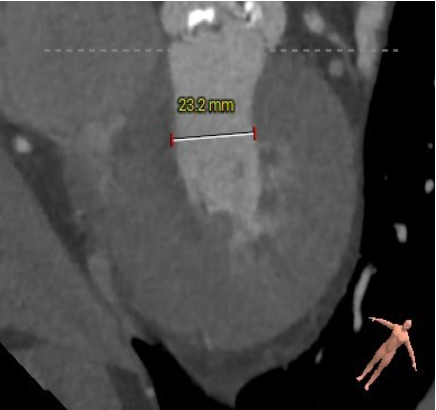

主动脉根部测量

ANNULUS

CT数据显示该患者为Type1型主动脉瓣。